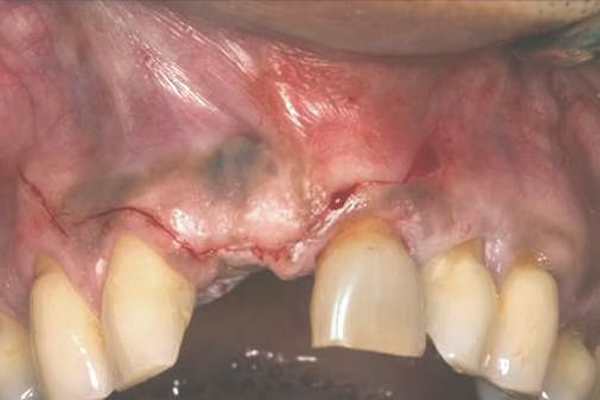

Fig 17. Vertical and horizontal incisions were sutured to attain primary closure.

Figure 17